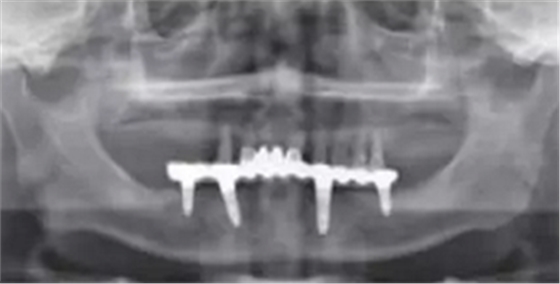

術后曲面斷層全景片(圖19)可見種植體在上頜位置較為理想,同時可見臨時義齒種植體開孔位置在13、23舌側、16、26牙合面近中,上下頜咬合關系理想。患者對種植臨時修復義齒滿意。

圖19 即刻修復后全景片